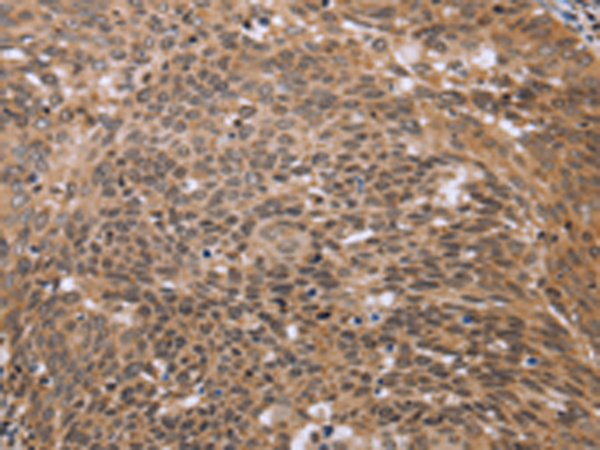

分类: 科研抗体货号: P08288别名:应用: IHC反应种属: Human, Mouse